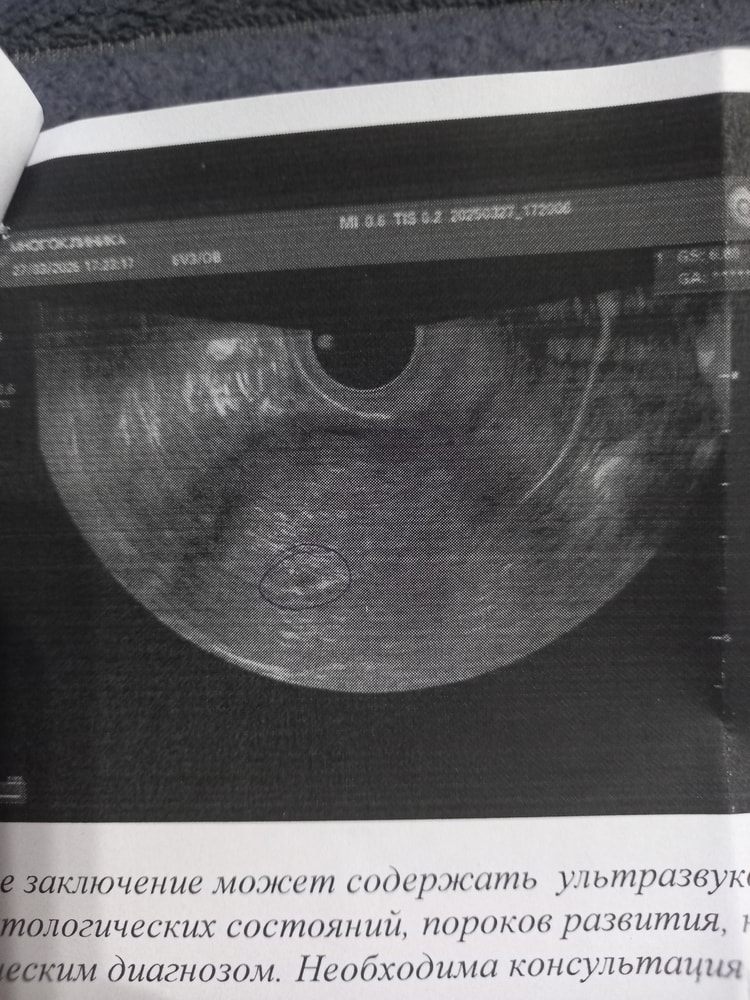

Юленька, выше это не похоже на яйцо,возможно узист сама придумала что там яйцо,а вы только забеременели

Маруся, Изображение

Юленька, в общем ждём следующего результата хгч,если вырастет минимум в 2 раза идите в клинику и требуйте деньги назад,какое яйцо она там нашла,соответствующее 5 неделям?вопрос встанет о некачественно оказанной услуге

Маруся, по яйцу что то пробурчала, что похоже на 3-4 недели

При хгч 72 не могли найти плодное яйцо,плодное яйцо 2-3 мм в диаметре видно при хгч от тысячи,а есть протокол УЗИ с описанием? Овуляция то может и поздняя хгч соответствует примерно 13 дню от овуляции,как раз и с па совпадает,но по УЗИ на таком сроке пя не видно ни у кого,ошиблись с пя,это рано

Марина, она сначала вообще не могла его найти, ковырялась там, как в кармане, ещё какие то 2 штуки там нашла по 6 миллиметров. Короче, жду следующего хгч, если вырастет, на другое узи, мало ли

Юленька, что-то не то она нашла,у меня пя 8 мм было и хгч 7200 за 2 дня до УЗИ,с таким хгч 72 пя меньше 1 мм и никакое УЗИ его не рассмотрит и нет смысла сейчас ходить,надо хгч в динамике посмотреть,если вырастет хорошо,то значит поздняя овуляция

Юленька, может желтое тело она нашла?

Наташа, Изображениеяйцо где то тут

Юленька, это не яйцо 100% его ещё в проекте нет,здесь есть фото с отрицательным хгч и пя по УЗИ,но там прям очень похоже на пя,а у вас даже не похоже,но в итоге тоже не пя,а х.з что они там за него приняли